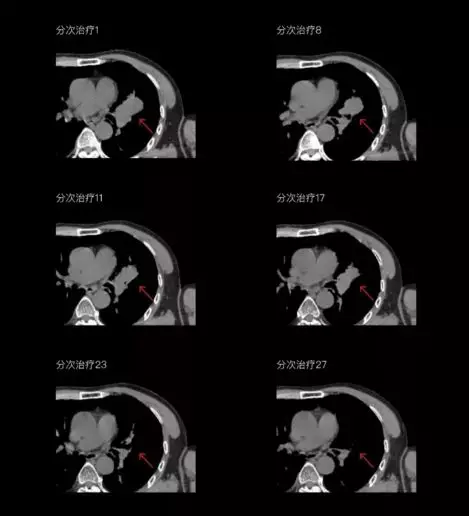

一體化CT-linac讓自適應(yīng)放療ART概念變?yōu)楝F(xiàn)實(shí)?;颊呷煶虪顟B(tài)監(jiān)控,適時(shí)在線調(diào)整治療計(jì)劃,精準(zhǔn)控制治療劑量,為患者動(dòng)態(tài)定制個(gè)體化治療方案。uAI賦能智能勾畫和自動(dòng)計(jì)劃,秒級(jí)勾勒靶區(qū)和危及器官,大幅縮短自適應(yīng)放療時(shí)間。

聯(lián)影CT-linac全程監(jiān)測(cè)治療過(guò)程病灶的變化,及時(shí)調(diào)整和優(yōu)化治療方案